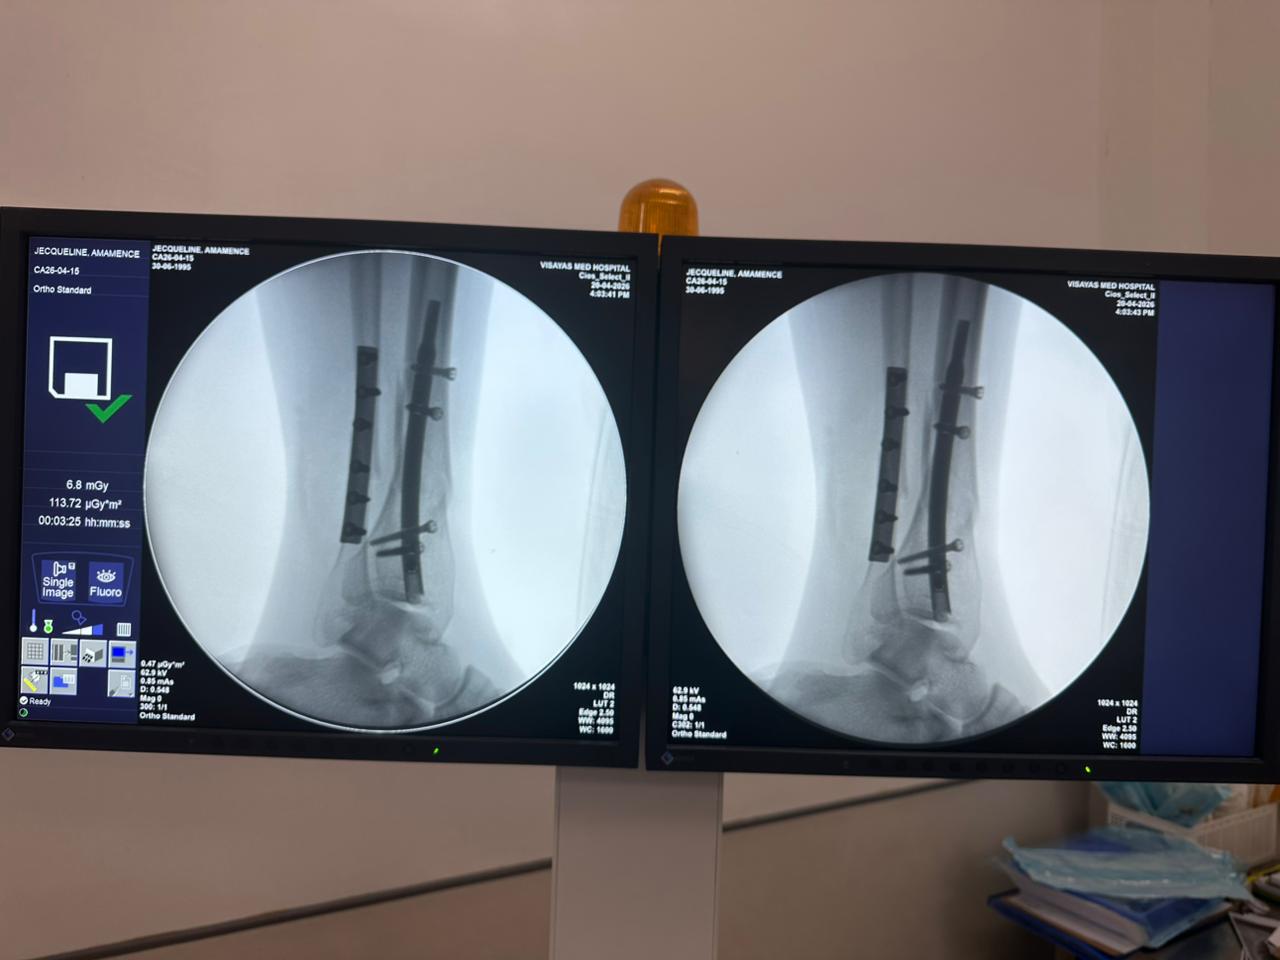

Caso di studio sulla fissazione del chiodo tibiale distale con supporto per placca peroneale

Fluoroscopia intraoperatoria con arco a C, viste AP e laterali

Questo caso prevedeva la fissazione tibiale distale utilizzando un chiodo tibiale distale intramidollare. La fluoroscopia intraoperatoria ha confermato la posizione del chiodo, delle viti di bloccaggio distali e della fissazione della placca peroneale.